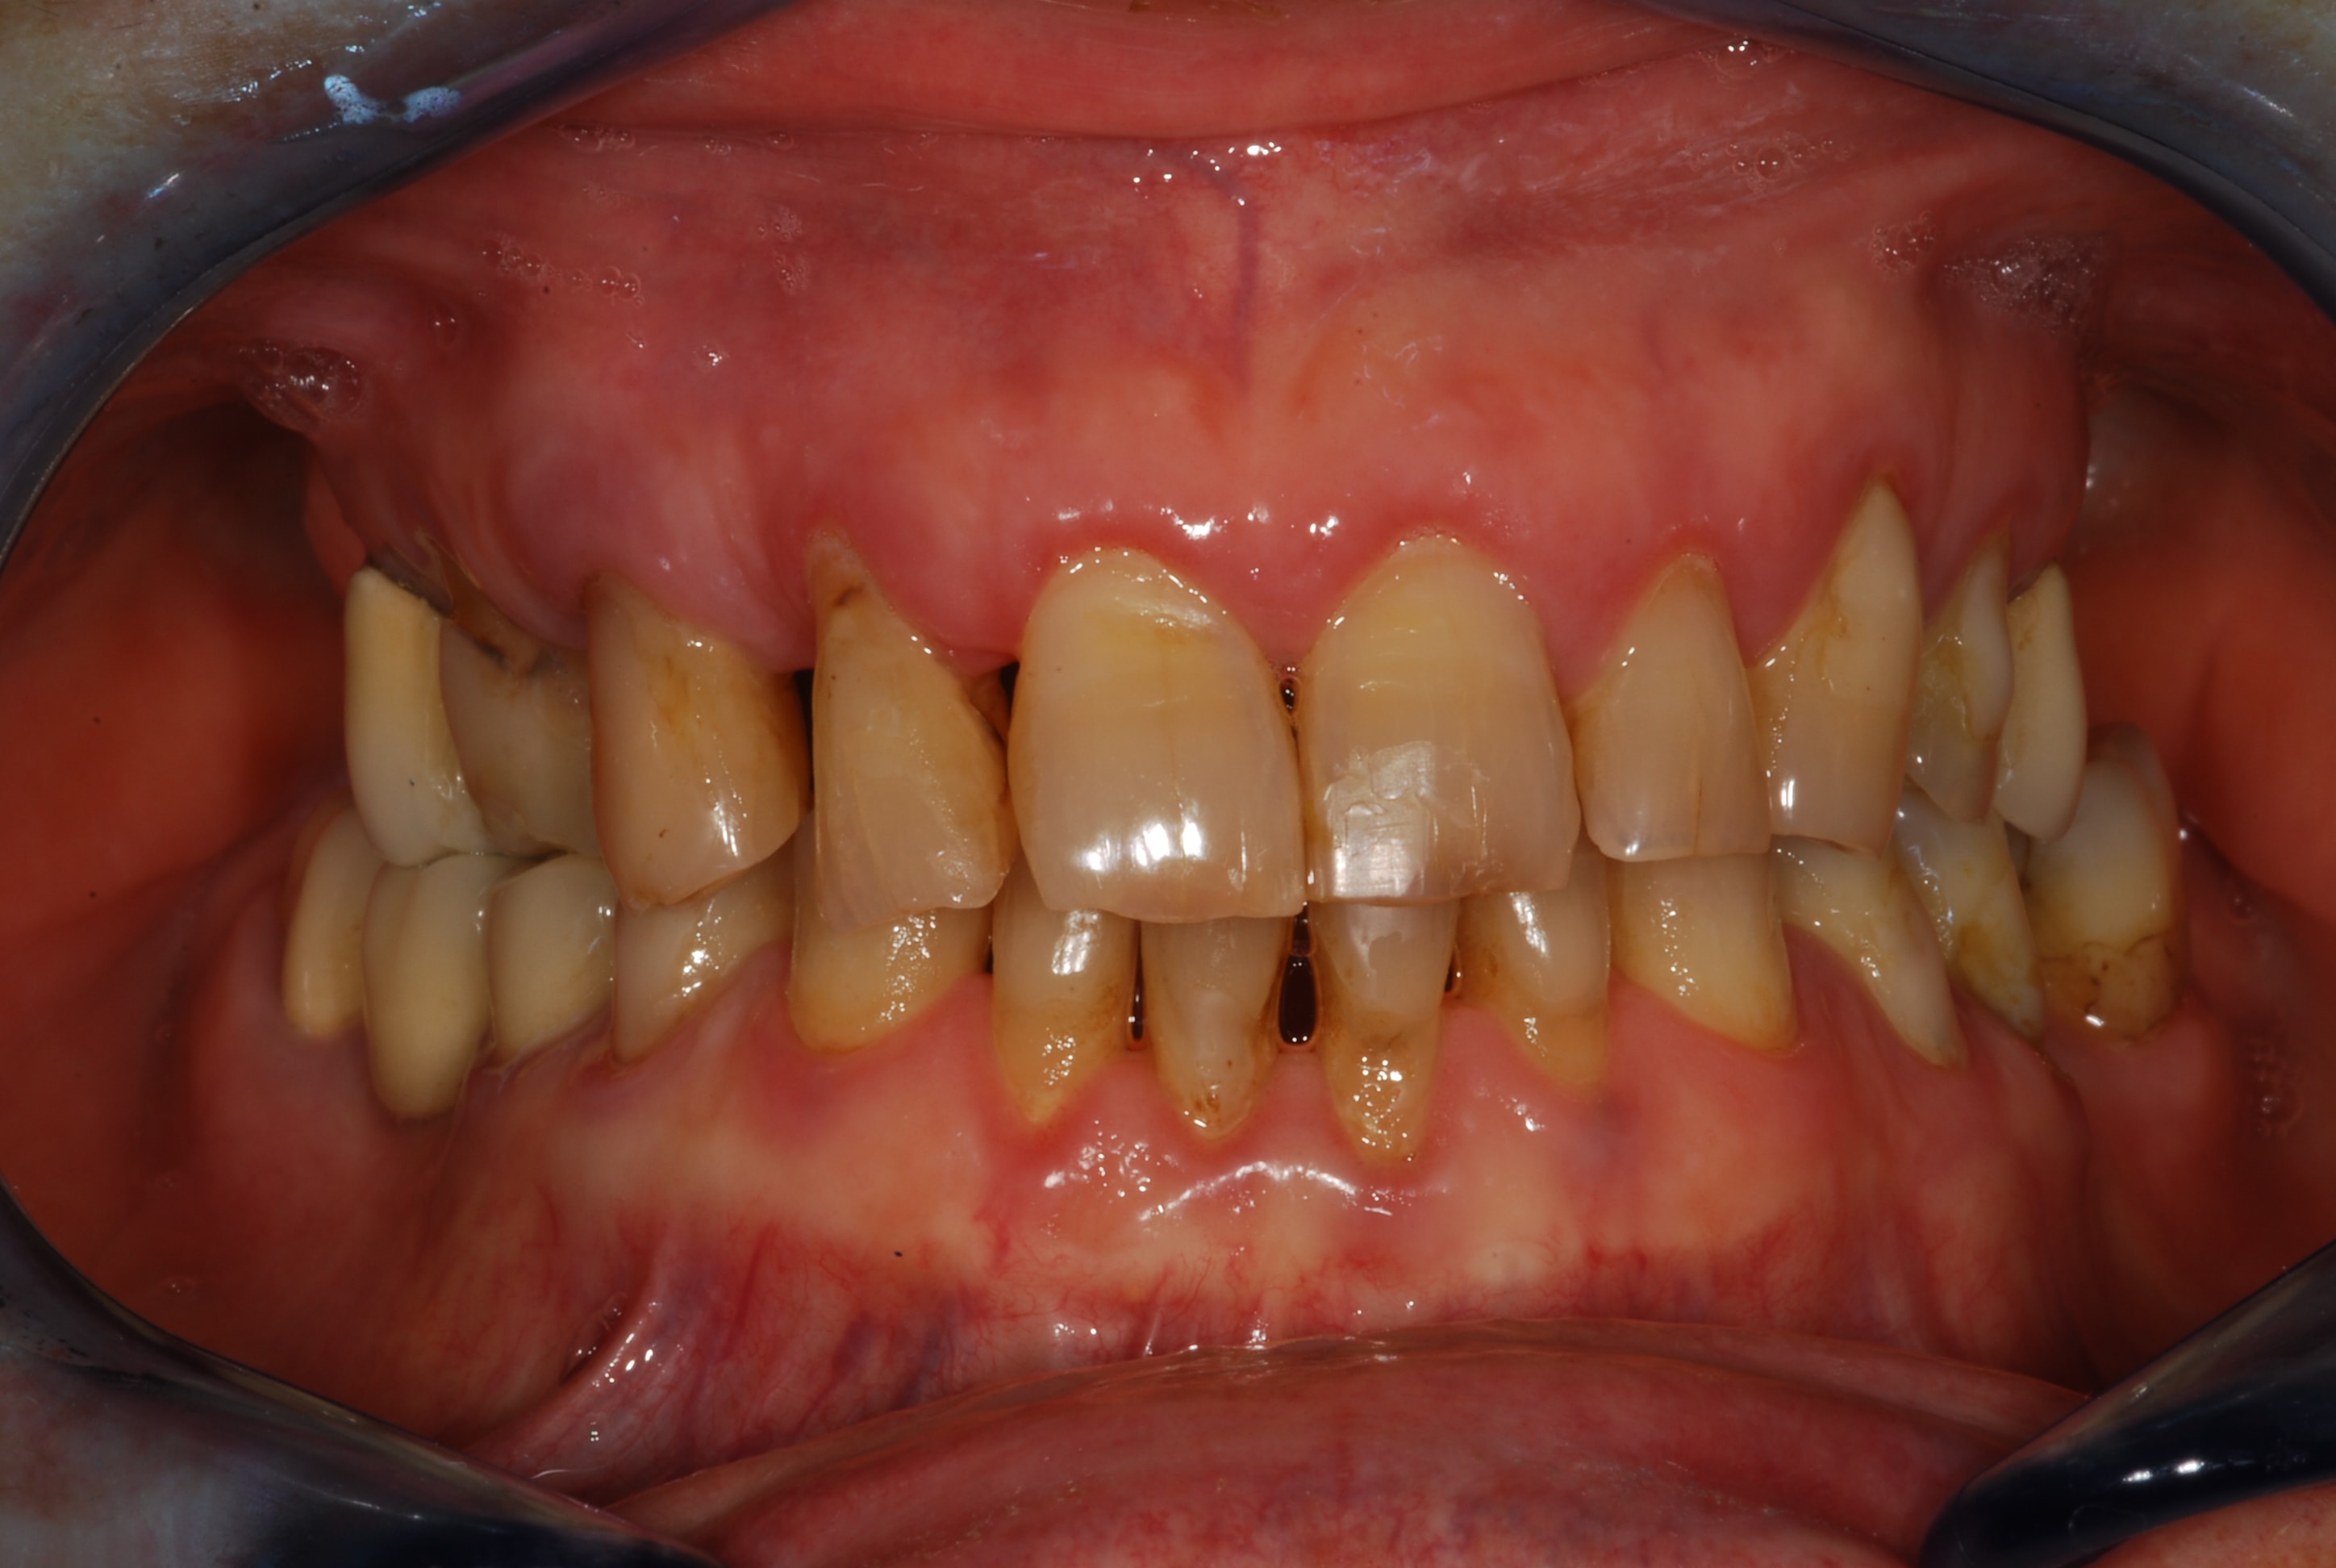

Bonjour à tous,

Voici comme prévu les photo du cas, j'ai pris les empreintes ce jour donc je posterais des photos des moulages dès que le proto les aura coulés !

Esthétique... Combler les diastèmes, teinte etc. et accessoirement pérenniser ses dents...

je suppose que le pt inter incisif n est pas au milieu de la figure , je me trompe ?

on dirait que le secteur 20 est parti à gauche , y compris la 11 , et qu a partir de la 11 le secteur 10 s est vestibulé . donc je confirme que tu ne peux faire le haut sans le bas .